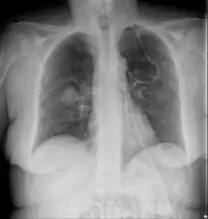

Chest X-ray: likely fungal infection left lung in an immunocompromised person

CT scan chest of person treated for acute myeloid leukaemia, presented with cough, fever and shortness of breath.